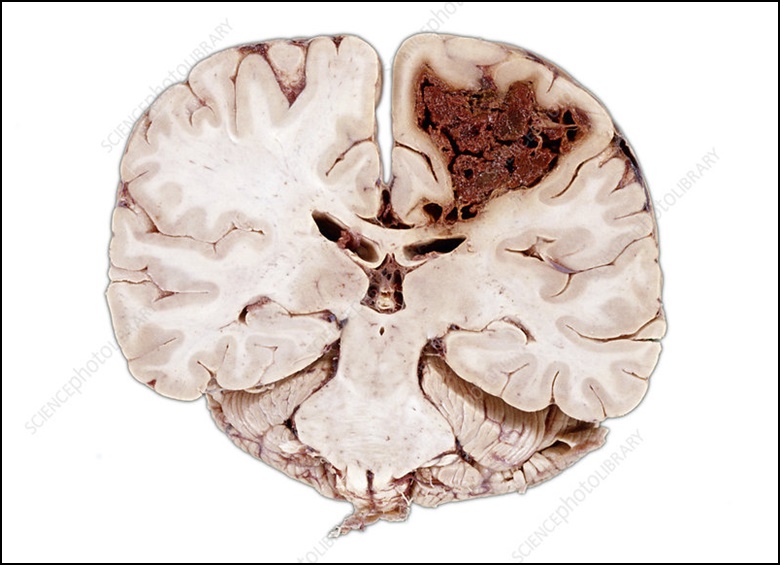

뇌경색은 뇌의 혈류 감소가 일정 시간 지속되면서, 뇌조직의 괴사가 발생되어 회복이 불가한 상태가 되었을 때를 뜻합니다. 뇌의 혈류 감소로 인해 뇌 기능에 이상이 발생되었지만 적절하게 치료를 통해 충분한 뇌의 혈류가 다시 공급되어 뇌의 조직이 시가 없이 뇌의 기능이 회복되는 경우도 있는데 이를 일과성 허혈성 발작이라고 부르고 있습니다. 오늘은 뇌경색 초기 증상 및 원인 치료방법에 대해서 알아보도록 하겠습니다.

골든타임을 놓쳐 뇌세포 괴사가 시작된 경우 뇌경색 치료는 혈관을 뚫게 되는데 혈관을 다시 뚫는다고 해도 후유증이 심각하게 남거나 악화될 수 있으며 심한 경우 사망에 이르는 경우도 적지 않습니다.